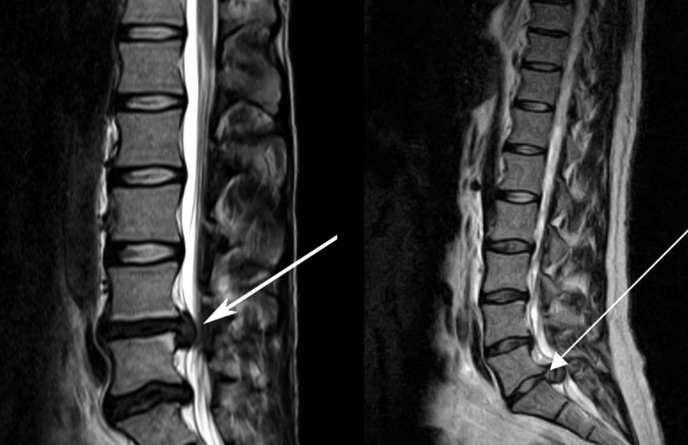

![]() 關(guān)于腰椎間盤(pán)突出 ![]() 腰椎間盤(pán)突出癥是纖維環(huán)破裂后髓核突出壓迫神經(jīng)根造成以腰腿痛為主要表現(xiàn)的疾病。腰椎間盤(pán)退行性改變或外傷所致纖維環(huán)破裂,髓核從破裂處脫出,壓迫腰椎神經(jīng),從而出現(xiàn)腰腿放射性疼痛。 ![]() 病因: 一、退行性變: 目前認(rèn)為,其基本病因是腰椎間盤(pán)的退行性變。退行性變是一切生物生、長(zhǎng)、衰、亡的客觀規(guī)律,由于腰椎所承擔(dān)的特殊的生理功能,腰椎間盤(pán)的退行性變比 其他組織器官要早,而且進(jìn)展相對(duì)要快。這個(gè)過(guò)程是一個(gè)長(zhǎng)期,復(fù)雜的過(guò)程。所謂腰椎間盤(pán)退行性改變:即由于椎間盤(pán)受體重的壓迫,加上腰部又經(jīng)常進(jìn)行彎曲、后伸等活動(dòng),易造成椎間盤(pán)的擠壓和磨損,尤其是下腰部的椎間盤(pán),從而產(chǎn)生退行性改變。腰椎間盤(pán)退行性改變是本病發(fā)生的基礎(chǔ)?!?/p> 二、其他因素: 1、外力作用:在日常生活和工作中,部分人往往存在長(zhǎng)期腰部用力不當(dāng)、過(guò)度用力姿勢(shì)或體位的不正確等情況。例如長(zhǎng)期從事彎腰工作的煤礦工人和建筑工人需經(jīng)常彎腰提舉重物。這些長(zhǎng)期反復(fù)的外力造成的損傷日積月累地作用于椎間盤(pán),加重了退變的程度。 2、椎間盤(pán)自身解剖因素的弱點(diǎn): (1) 椎間盤(pán)在成人之后逐漸缺乏血液循環(huán),修復(fù)能力也較差,特別是在退變產(chǎn)生后,修復(fù)能力更加微弱。 (2) 椎間盤(pán)后外側(cè)的纖維環(huán)較為薄弱,而后縱韌帶在腰5、骶1平面時(shí)寬度顯著減少,對(duì)纖維環(huán)的加強(qiáng)作用明顯減弱。 (3) 腰骶段先天異常:腰骶段畸形可使發(fā)病率增高,這些異常造成椎間隙寬度不等,并常造成關(guān)節(jié)突出,關(guān)節(jié)受到更多的旋轉(zhuǎn)勞損,使纖維環(huán)受到的壓力不一,加速退變。 3、種族、遺傳因素:有色人種發(fā)病率較低,例如印第安人和非洲黑人等發(fā)病率較其他民族明顯要低。 ![]() 2 病理 腰椎間盤(pán)突出癥的病理變化過(guò)程大致可分為三個(gè)階段: 1、突出前期:髓核因退變和損傷可變成碎塊狀物,或呈瘢痕樣結(jié)締組織,變性的纖維環(huán)可因反復(fù)損傷而變薄變軟或產(chǎn)生裂隙。此期病人可有腰部不適或疼痛,但無(wú)放射性下肢痛。也有的人原無(wú)病變,可因一次大的暴力引起髓核突出。 2、突出期:外傷或正常的活動(dòng)使椎間盤(pán)壓力增加時(shí),髓核從纖維環(huán)薄弱處或破裂處突出。突出物刺激或壓迫神經(jīng)根即發(fā)生放射性下肢痛,或壓迫馬尾神經(jīng)發(fā)生大小便功能障礙。在老 年患者,可因椎間盤(pán)退變,整個(gè)纖維環(huán)變得軟弱松弛,椎間盤(pán)可呈彌漫性向周?chē)虺觥?/p> 3、突出晚期:腰椎間盤(pán)突出后,病程較長(zhǎng)者,椎間盤(pán)本身和其他鄰近結(jié)構(gòu)均可發(fā)生各種繼發(fā)性病理改變。 3 誘發(fā)因素 腰椎間盤(pán)突出癥的基本因素是椎間盤(pán)退變,但某些誘發(fā)因素可致使椎間隙壓力增高,引起髓核突出。此種誘發(fā)因素常與以下因素有關(guān): 1. 年齡因素:腰椎間盤(pán)突出癥的好發(fā)年齡在30-50歲,平均手術(shù)年齡在40歲,因此退變可能是其重要因素。 2. 身高與性別:有人認(rèn)為身材過(guò)高也會(huì)易發(fā)腰突癥,而男性發(fā)病率是女性的5倍?!?/p> 3. 增加腹壓:臨床上有約1/3的病人在發(fā)病前有明確的增加腹壓的因素,如劇烈的咳嗽、噴嚏、屏氣、用力排便等。使腹壓增高,破壞了椎節(jié)與椎管之間的平衡狀態(tài)。 4. 不良體位:人在完成各種工作時(shí),需要不斷更換各種體位以緩解腰部壓力,如長(zhǎng)期處于某一體位不變,即可導(dǎo)致局部的累積性損傷。特別是長(zhǎng)期處于不良姿勢(shì)更容易誘發(fā)本病。 5. 職業(yè)因素:重體力勞動(dòng)者發(fā)病率最高,白領(lǐng)勞動(dòng)者最低。汽車(chē)駕駛員由于長(zhǎng)期處于顛簸和振動(dòng)狀態(tài),椎間盤(pán)承受的壓力大且反復(fù)變化,也易誘發(fā)椎間盤(pán)突出?!?/p> 6. 受寒受濕:寒冷或潮濕可引起小血管收縮、肌肉痙攣,使椎間盤(pán)的壓力增加,可能造成退變的椎間盤(pán)破裂。 ![]() ![]() ![]() ![]() 癥狀: 腰椎間盤(pán)突出癥患者最多見(jiàn)的癥狀為疼痛,可表現(xiàn)為腰背痛、坐骨神經(jīng)痛,典型的坐骨神經(jīng)痛表現(xiàn)為由臀部、大腿后側(cè)、小腿外側(cè)至跟部或足背的放射痛。據(jù)臨床統(tǒng)計(jì),約95%的腰突癥患者有不同程度的腰痛,80%的患者有下肢痛。特別是腰痛,不僅是腰椎間盤(pán)突出最常見(jiàn)的癥狀,也是最早出現(xiàn)的癥狀之一。 ![]() ![]() ![]() 檢查: 1、X線:腰椎間盤(pán)所包括的髓核、纖維環(huán)和軟骨板密度均較低,在X線下并不顯影,因此臨床上腰突癥患者的腰椎X線平片可僅有一些非特異性的變化,甚至無(wú)異常變化。因此單純腰椎平片并不能作為有無(wú)腰椎間盤(pán)突出癥的直接依據(jù),但X線能發(fā)現(xiàn)腰椎的退行性改變和結(jié)構(gòu)異常,對(duì)提示椎間盤(pán)的退變有重要意義,并且能排除其他的一些腰椎疾患,如腰椎結(jié)核、腫瘤和腰椎滑脫等。典型的腰椎間盤(pán)突出癥患者通過(guò)病史、體征和X線平片即能作出初步的診斷?!?/p> 2、CT檢查:腰椎的CT可以清楚地顯示椎間盤(pán)突出的部位、大小、形態(tài)和神經(jīng)根、硬脊膜受壓的情況,同時(shí)還可顯示黃韌帶肥厚、小關(guān)節(jié)增生、椎管和側(cè)隱窩狹窄等情況。對(duì)腰椎間盤(pán)突出癥診斷的準(zhǔn)確率達(dá)到80%-92%?!?/p> 3、核磁共振(MRI):核磁共振沒(méi)有輻射,可以多方位成像(橫斷面、冠狀面、矢狀面和斜面),對(duì)解剖細(xì)節(jié)顯示較好,對(duì)組織結(jié)構(gòu)的細(xì)微病理變化更敏感(如骨髓的浸潤(rùn)),可以排除神經(jīng)和脊柱腫瘤等。對(duì)于一些落到椎管的髓核組織也不會(huì)遺漏。 4、脊髓造影:脊髓造影利用椎管內(nèi)蛛網(wǎng)膜下腔的空隙,注入造影劑后在X線下攝片,顯示椎管內(nèi)部結(jié)構(gòu)。目前常用水溶性造影劑,能較清晰地顯示硬膜腔、馬尾神經(jīng)和神經(jīng)根鞘,對(duì)腰椎間盤(pán)突出癥的診斷可達(dá)90%左右,主要X線表現(xiàn)為硬膜囊壓迫征象和神經(jīng)根鞘壓迫征象。但由于CT和MRI在臨床的廣泛應(yīng)用,無(wú)創(chuàng)傷且診斷率更高,脊髓造影在臨床上的應(yīng)用已經(jīng)大大減少,而且由于它副作用較大,甚至可能造成截癱等嚴(yán)重情況,目前主張慎重選用。 5、肌電圖:肌電圖是對(duì)周?chē)窠?jīng)與肌肉的電生理檢查方法,可用于觀察并記錄肌肉在靜止、主動(dòng)收縮和支配其的周?chē)窠?jīng)受刺激時(shí)的電活動(dòng),同時(shí)也可用來(lái)測(cè)量周?chē)窠?jīng)的傳導(dǎo)速度。在腰椎間盤(pán)突出癥上,肌電圖主要通過(guò)檢查雙下肢肌肉的興奮性來(lái)反映相應(yīng)神經(jīng)根的狀態(tài),并根據(jù)異常電活動(dòng)的分布范圍來(lái)判斷椎間盤(pán)突出和神經(jīng)根受壓的節(jié)段。在脊神經(jīng)根和馬尾神經(jīng)受壓的病人,肌電圖陽(yáng)性率可達(dá)80%-90%,但與CT和MRI相比并不是首選的檢查手段,可用于輔助診斷和判斷神經(jīng)根的受壓情況,同時(shí)也可以用來(lái)作為判斷治療后神經(jīng)根恢復(fù)情況的指標(biāo)之一。 ![]() ![]() ![]() 預(yù)防: 腰椎間盤(pán)突出癥是在退行性變基礎(chǔ)上積累傷所致,積累傷又會(huì)加重椎間盤(pán)的退變,因此預(yù)防的重點(diǎn)在于減少積累傷。 日常注意事項(xiàng): 1.平時(shí)要有良好的坐姿,睡眠時(shí)的床不宜太軟。 2.長(zhǎng)期伏案工作者需要注意桌、椅高度,定期改變姿勢(shì)。 3.職業(yè)工作中需要常彎腰動(dòng)作者,應(yīng)定時(shí)伸腰、挺胸活動(dòng),并使用寬的腰帶。 4.應(yīng)加強(qiáng)腰背肌訓(xùn)練,增加脊柱的內(nèi)在穩(wěn)定性,長(zhǎng)期使用腰圍者,尤其需要注意腰背肌鍛煉,以防止失用性肌肉萎縮帶來(lái)不良后果。 5.如需彎腰取物,最好采用屈髖、屈膝下蹲方式,減少對(duì)腰椎間盤(pán)后方的壓力。 ![]() ![]() ![]() 治療: (一)中醫(yī)外敷療法: 腰椎間盤(pán)突出可以外貼 腰突正骨膏,其有效成分可透入皮膚產(chǎn)生活血,止痛,化淤,通經(jīng)走絡(luò),開(kāi)竅透骨,祛風(fēng)散寒等效果,并通過(guò)藥物的歸經(jīng)作用而調(diào)理機(jī)體陰陽(yáng)平衡,滲透于表皮,刺激神經(jīng)末梢,促進(jìn)局部血液微循環(huán),扶正固本、改善體質(zhì),從根本上、全方位針對(duì)腰椎疾病病機(jī)特點(diǎn)而發(fā)揮療效,改善病變周?chē)M織營(yíng)養(yǎng),起到修復(fù)骨病組織的作用,最終達(dá)到治療目的。 (二)自我治療: 1.腹肌鍛煉: 也就是仰臥起坐。每次做十個(gè),每天三次。(可根據(jù)患者的體質(zhì)來(lái)定,不可逞強(qiáng))。 2.交叉扭腰: 兩腳分開(kāi)與肩寬,腳尖向內(nèi)兩臂伸直,一手在體側(cè),一 手舉過(guò)頭頂。如果右手在上,先向左側(cè)后方擺。左側(cè)相反。于此同時(shí)腰部也隨之扭動(dòng),左右各100次。 3.抱膝觸胸: 處于仰臥位,雙膝屈曲,手抱住膝部,使盡量靠近胸部,然后放下,一上一下為一個(gè)動(dòng)作,可持續(xù)30個(gè)。 4.腰背肌鍛煉: 處于平臥,雙膝彎曲放在床上,然后用力將臀部抬起,離開(kāi)床面10厘米。這時(shí)您會(huì)感覺(jué)到腰背部在用力,堅(jiān)持5秒鐘,反復(fù)10下。 ![]() (三)非手術(shù)治療: 非手術(shù)療法是治療腰椎間盤(pán)突出癥的基本療法,約80%以上的患者經(jīng)保守治療均可得到緩解和痊愈。其主要療法有: 1.日常家庭治療:早期腰椎間盤(pán)突出癥,癥狀輕微,不需要做特殊的治療。第一,注意臥床休息,避免腰椎受外力壓迫,第二,應(yīng)用其他方法積極鍛煉腰部肌肉力量。 2.牽引治療; 3.推拿按摩治療; 4.物理治療; 5.消炎鎮(zhèn)痛藥物; 6.減輕神經(jīng)根水腫藥物。 (四)推拿治療: 1.解除腰臀部肌肉痙攣 2.拉寬椎間隙,降低盤(pán)間壓力 3.增加椎間盤(pán)外壓力 4.調(diào)整后關(guān)節(jié),松解粘連 5.促使受損傷的神經(jīng)根恢復(fù)功能 (五)微創(chuàng)治療: 微創(chuàng)治療方法的目的是消除腰椎間盤(pán)突出的髓核以解除對(duì)神經(jīng)的壓迫。微創(chuàng)治療技術(shù)采用可視設(shè)備,創(chuàng)口不足一厘米有些甚至不足一毫米。消融或摘除髓核,從根本上解除致病因素,因而能夠取得很好的效果。 (六)手術(shù)治療: 腰椎間盤(pán)突出癥的手術(shù)原則是嚴(yán)格無(wú)菌操作,盡量保留不必去除的骨結(jié)構(gòu)和軟組織結(jié)構(gòu),以最小的創(chuàng)傷達(dá)到足夠的顯露,仔細(xì)徹底地去除病變組織,達(dá)到治療目的。 ![]() ![]() 綠柏相關(guān)產(chǎn)品: ![]() 懸吊訓(xùn)練療法是康復(fù)醫(yī)學(xué)中以持久改善肌肉骨骼疾病為目的的,應(yīng)用主動(dòng)治療和訓(xùn)練的一個(gè)總的概念整合,是一種運(yùn)動(dòng)感覺(jué)的綜合訓(xùn)練系統(tǒng),包括診斷與治療兩大系統(tǒng)。 產(chǎn)品特點(diǎn): 1.電腦軟件管理系統(tǒng),涵蓋患者信息管理、評(píng)估、訓(xùn)練、量表、報(bào)告、視頻教學(xué)六大模塊,輕松實(shí)現(xiàn)評(píng)估與訓(xùn)練一體化管理; 2.多點(diǎn)多軸設(shè)計(jì),滿足不同治療方案設(shè)計(jì); 3.懸吊工作站及各個(gè)懸吊點(diǎn),均能實(shí)現(xiàn)任意位置移動(dòng),一鍵解鎖,省時(shí)省力; 4.實(shí)時(shí)力反饋,精準(zhǔn)量化弱鏈測(cè)試及懸吊治療全過(guò)程,給治療師及患者最直觀的效果呈現(xiàn); 5.智能神經(jīng)肌肉促通裝置,可根據(jù)評(píng)估結(jié)果設(shè)置治療模式、頻率、時(shí)間等相關(guān)參數(shù),讓?xiě)业蹩祻?fù)更加高效有針對(duì)性; 6.外觀高端大氣,結(jié)構(gòu)穩(wěn)固,給患者安全保障,增加治療信心。 ![]() |